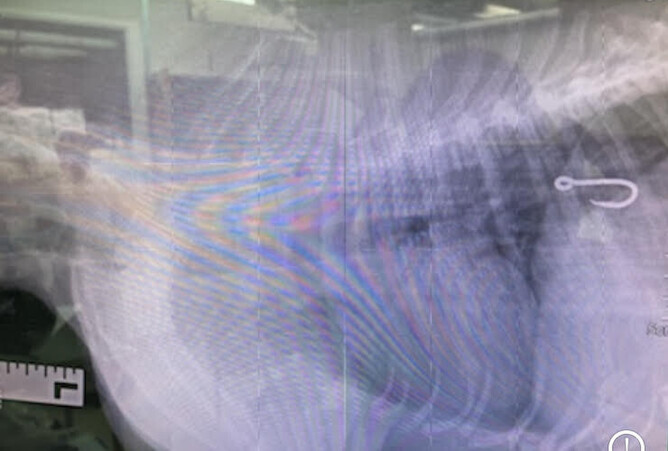

Was the hook still in her mouth? Was it stuck in her oesophagus? Or had it made its way to her stomach? Was the bait still on the hook? Had the hook damaged anything on the way down? These were the first questions we had to find the answers to before we could even begin to establish whether we could remove it or not. After Raven’s initial physical examination, we took an X-ray to try and locate the whereabouts of the dreaded fish hook.

Raven went into surgery that night with Minnie and TJ, and the fish hook was successfully removed, with bait still attached, from Raven’s stomach. By 11.45pm, Raven was in recovery. A week later, she is doing amazingly well. She is one very lucky puppy. If her human family hadn’t seen her eat it, or if the hook didn’t have any fishing line attached, her beach food scavenging may have gone unnoticed, which would have had dire consequences.